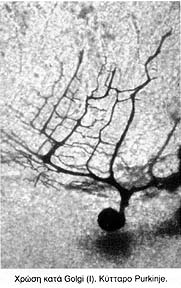

Μικροσκοπικά κατά τη δομή του παρεγκεφαλιδικού φλοιού δια αιματοξυλίνης εωσίνης διεπιστώθει ότι τα κύτταρα Purkinje ήταν ρικνά με πυκνοχρωματικό πυρήνα και εντυπωσιακό περιορισμό των τιγροειδών σωματίων στο περικάρυο των εν λόγω κυττάρων. Παράλληλα διαπιστώθηκε ότι ο κορυφαίος δενδρίτης εκφύετο δια αποπεπλατυσμένης βάσης και πριν εισέλθει στο κάτω τριτημόριο της μοριώδους στιβάδας διχάζετο σε ευμεγέθεις πτωτογενείς κλάδους οι οποίοι τοξοειδώς εφέροντο προς τα έξω και άνω, μέχρι των ορίων του μέσου και έξω τριτημορίου της μοριώδους στιβάδας.

Εντυπωσιακή ήταν η μορφολογία των κυττάρων δια της μεθόδου κατά Golgi. Τα κύτταρα παρουσίαζαν βραχύ και λίαν πεπαχυμένο πρωτογενή κορυφαίο δενδρίτη ο οποίος έδινε ταχέως δύο ημικυκλικώς φερομένους δευτερογενείς κλάδους εκ των οποίων αναδύοντο βαραχείς τριγωνικές και ατρακτοειδείς άκανθες που ο αριθμός τους ήταν εμφανώς μικρότερος των υγιών μαρτύρων.

Το δενδριτικό δίκτυο των κυττάρων Purkinje δεν εκάλυπτε όλο το επίπεδο της μοριώδους στιβάδας με αποτέλεσμα το έξω τριτημόριο να καταλαμβάνεται από αστεροειδή κύτταρα.

Τα παράπλευρα παλίνδρομα αξονικά κλωνία ήταν ιδιαίτερα περιορισμένα με αποτέλεσμα να μην παρατηρείται το σύνηθες δίκτυο των παλινδρόμων κλωνίων υπό το σώμα των κυττάρων του Purkinje.